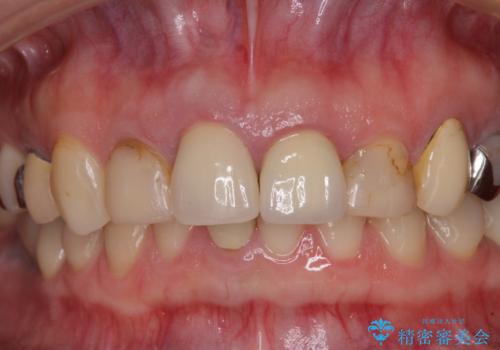

- 以前から前歯の根が折れていると言われていたものの放置しており、いよいよ痛みが気になってきたとのことで来院された患者様です。

検査の結果、右前歯の歯根が縦に破折していることが分かりました。

破折している歯は抜歯をし、歯肉が窪んでしまうので、傷口の治りを待って、歯肉移植を行うこととしました。

歯肉移植終了後、オールセラミックブリッジにて補綴することとしました。

歯肉移植により歯肉ラインや歯の形態を整えることができ、ブリッジによる補綴としたことで舞えば全体の色調を整えることができました。